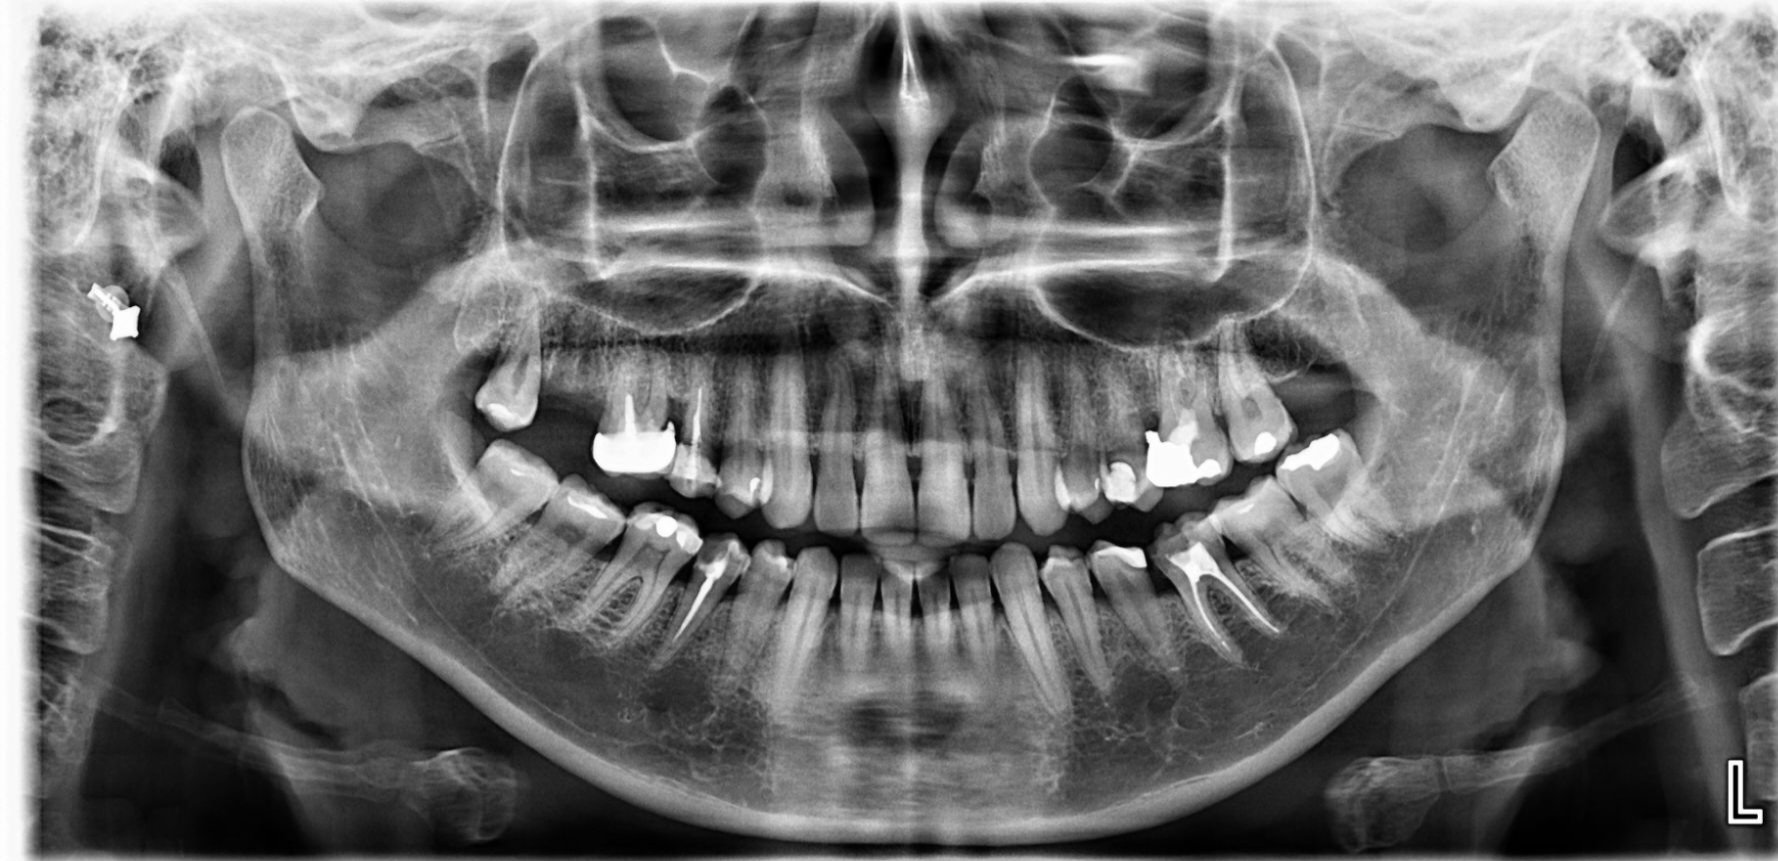

Здравейте д-р Маринов, имам сложен проблем, след недобро кореново лечение и поправки от неизчистен кариес(5ти ляв долен зъб,беше и леко крив ) получих пулсации около зъбите от 4ти наляво чак до венеца.Има миризма на гной, на снимка не излиза от къде е локализирана гнойта.Премахнаха ми зъба, но състоянието продължава.Пулсации без болка и миризма на гной от някъде в края.Може ли да каже на какво се дължи и как да се открие проблема?Имам отпадналост и сърцебиене, безапетитие от тогава.Възможно ли е около костта или в лигавицата на венеца да гнои или пък под съседни зъби да е преминало възпалението?Правихме дренаж и на венеца над мъдреца, не излиза нищо в дренаж.

До dreamgirl_89, добър ден. Най-вероятната причина за този дискомфорт е този мъдрец. Най-често там се събира храна и оттам започва тази миризма.